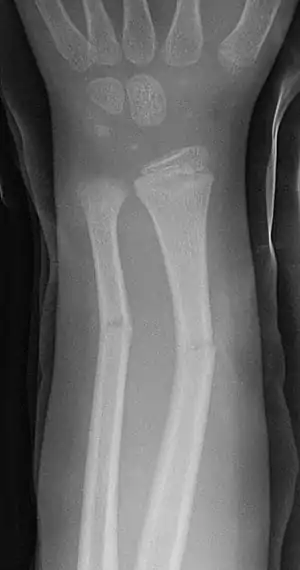

| Greenstick fractures on X-ray. | |

A greenstick fracture is a fracture in a young, soft bone in which the bone bends and breaks. Greenstick fractures occur most often during infancy and childhood when bones are soft. The name is by analogy with green (i.e., fresh) wood which similarly breaks on the outside when bent.

Projectional radiography is generally preferable.